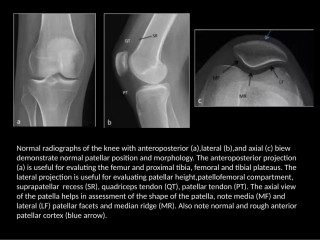

Normalradiographsofthekneewithanteroposterior(a),lateral(b),andaxial(c)biewdemonstratenormalpatellarpositionandmorphology.Theanter...